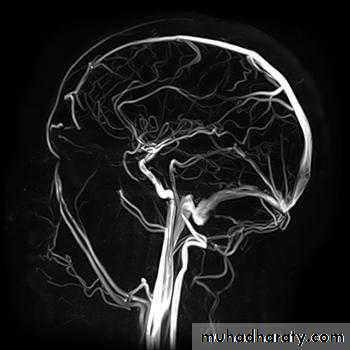

• Magnetic resonance angiography and magnetic resonance venography used for visualization of blood vessels with or without using contrast material.

• MRA is widely used in the imaging of the cerebral circulation and in some centers is the initial angiographic method of choice for other areas including the renal and peripheral circulations.